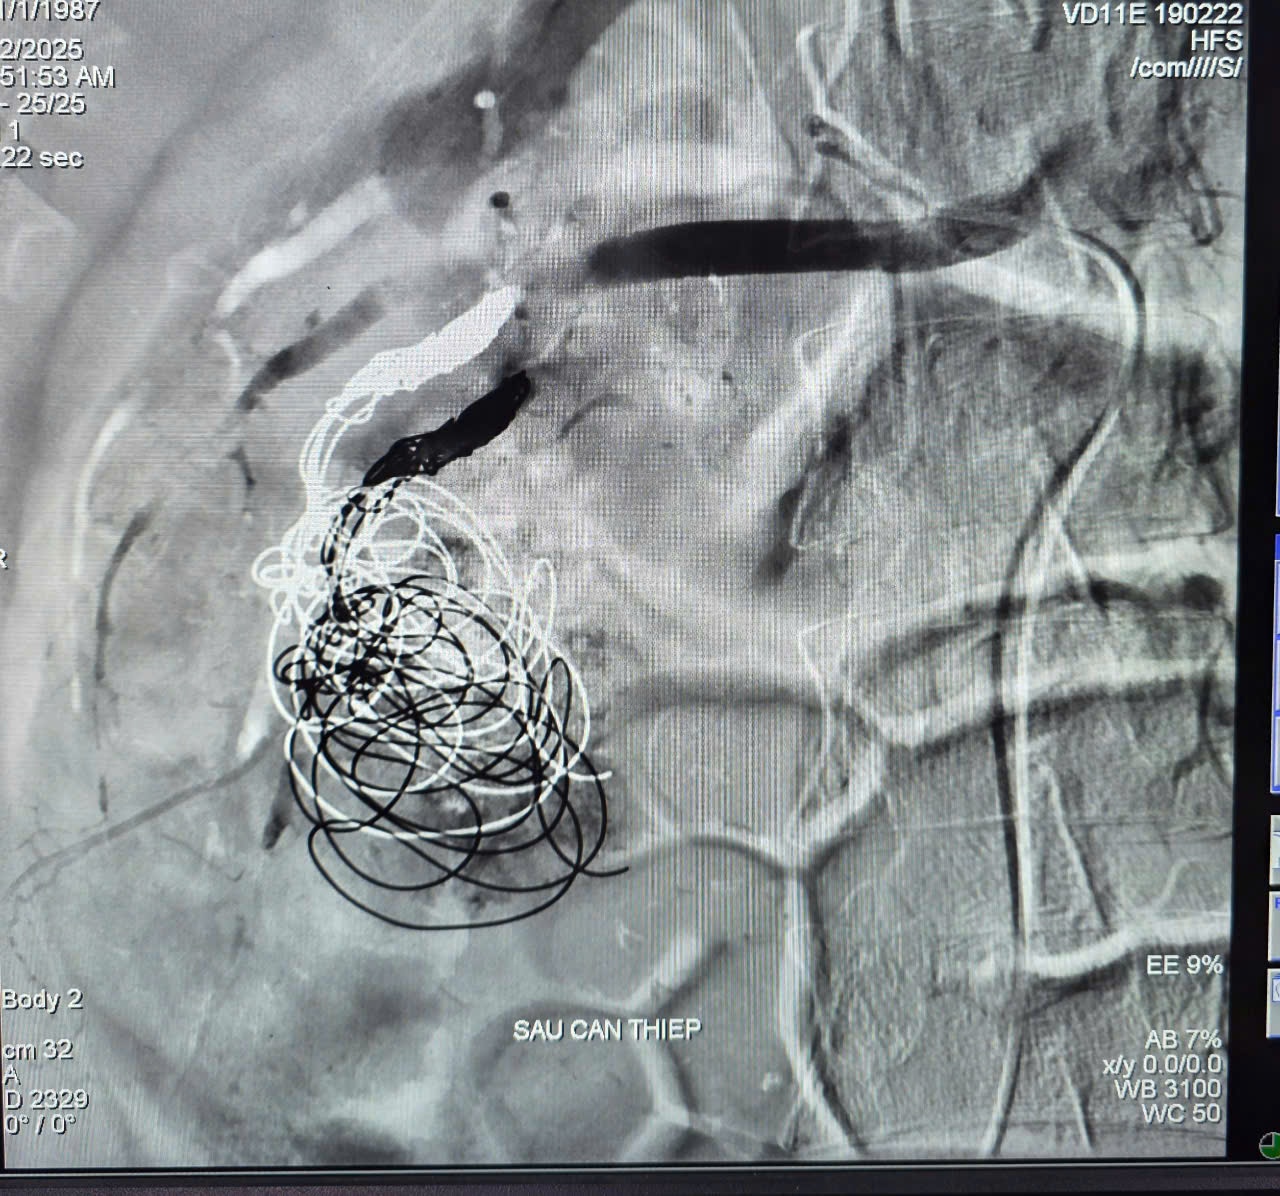

Ca can thiệp do BSCK2 Trần Công Khánh, Phó khoa Chẩn đoán hình ảnh cùng ê-kíp thực hiện. Kết quả cho thấy, ổ giả phình động mạch thận bên phải nhánh cực dưới có kích thước lớn và dòng chảy mạnh, luồn chọn lọc vi catheter vào nhánh động mạch có giả phình. Đây là một trường hợp can thiệp khó do phải tiến hành thả 4 coils và bơm tắc bằng hỗn hợp keo, thủ thuật trong 60 phút. Quá trình điều trị bệnh nhân được truyền 03 đơn vị khối hồng cầu.

Hình ảnh sau can thiệp bệnh nhân.